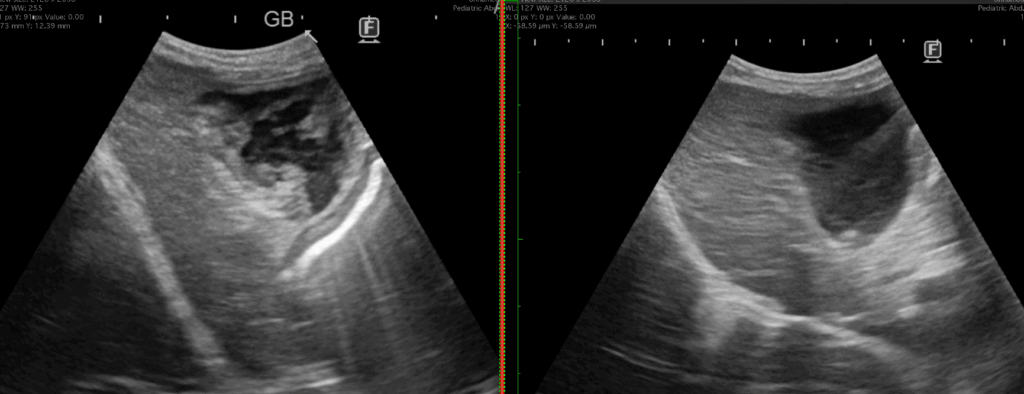

上記のエコー画像は冒頭の胆嚢摘出した症例の手術9か月前のエコー画像です。2枚とも同日です。

そんなに量は多くありませんが、胆嚢壁にはりつくような胆泥「重力非依存性胆泥」を認めます。

胆泥は①重力依存性胆泥 と ②重力非依存性胆泥 に分けて考えます。

①は重力方向に動くということです。

立位でエコーを見ると重力に従い腹側に溜まっていた胆泥が、仰向けにすると重力に従い背側に移動するなら重力依存性胆泥です。流動性胆泥とか可動性胆泥とか言われたら同じ意味です。

これを異常所見とすると、高齢犬の大半は異常になってしまいます。重力依存性胆泥にウルソを処方し続けることを当院では推奨していません。

問題は②です。

重力によって動かない壁にはりついたような胆泥です。これがある子がみんな粘液嚢腫化するかというと、そんなことはないと思います。ただ、①よりはリスクが高い状態と言えると思います。

今回このような症例を経験させていただいたので、当院では重力非依存性胆泥を認めた場合には、エビデンスは乏しいことを説明した上で、しかしながら、もし胆嚢粘液嚢腫になってしまうと命に関わるので少しでも可能性を下げたいとご希望いただけるのであれば、飼い主様に無理のない範囲での予防策をご提案するようにしようと思います。